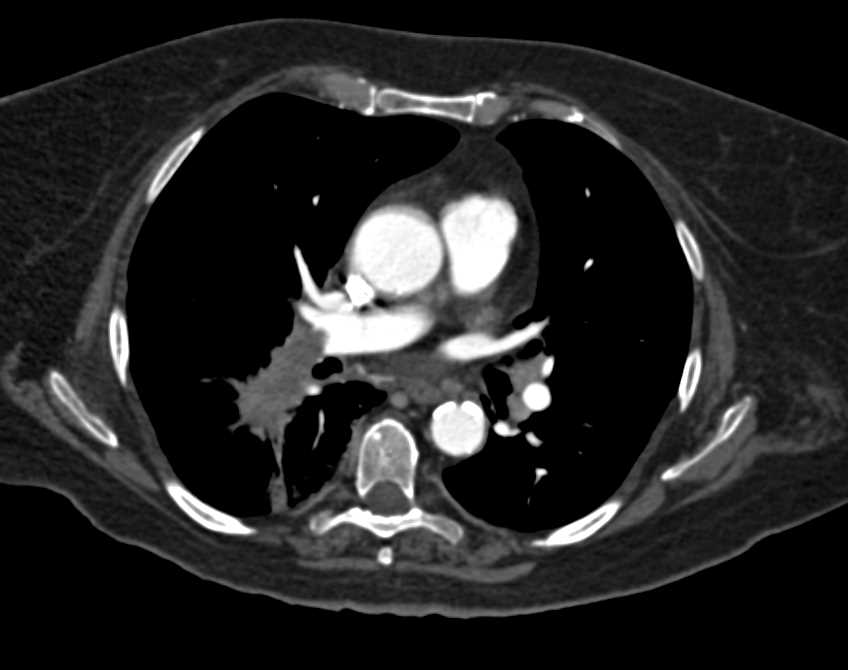

Aortic Valve Calcification with Aortic Stenosis as well as Pulmonary Embolism